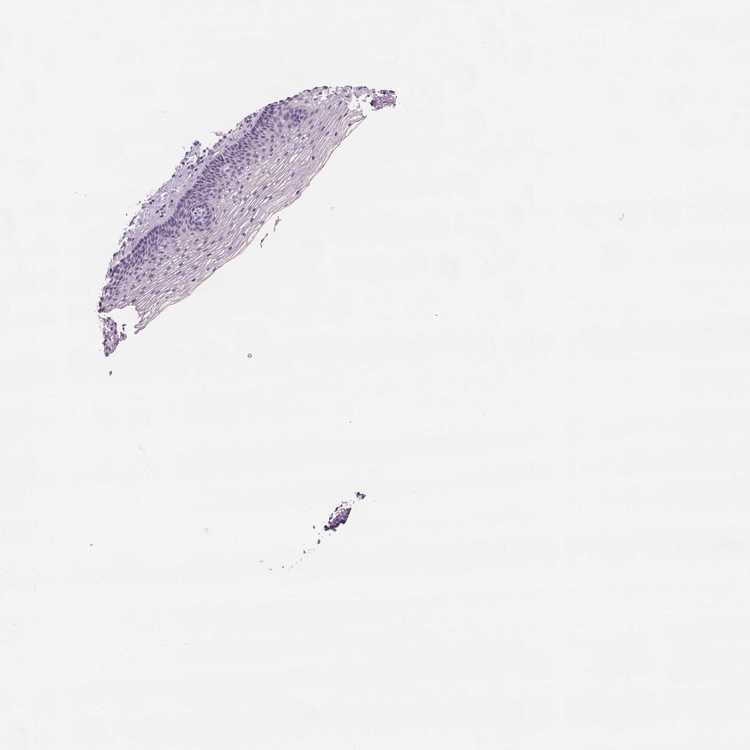

CERVIX - Antibody stainingi

Antibody staining in the annotated cell types in the current human tissue is reported as not detected, low, medium, or high, based on conventional immunohistochemistry profiling in selected tissues. This score is based on the combination of the staining intensity and fraction of stained cells.

Each image is clickable and will lead to virtual microscopy that enables deeper exploration of all samples and also displays staining intensity scores, fraction scores and subcellular localization as well as patient and tissue information for each sample.

Antibody HPA000452Antibody HPA000453Antibody HPA045062Antibody CAB000029

Squamous epithelial cells LowHighNot detectedNot detected